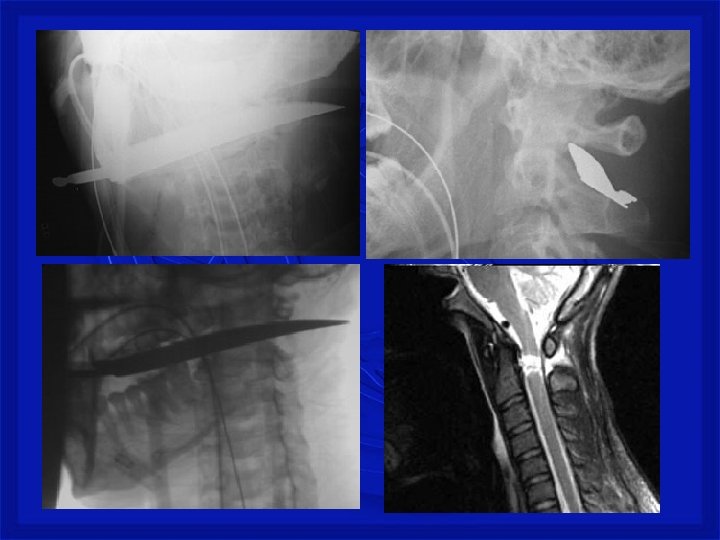

Mecanismo de Trauma Raqui. Medular Penetrante • Perfuração da coluna (arma branca, tiro ou estilhaço de bomba na coluna) • Lesão medular completa ou incompleta, associada ou não a lesão dos nervos espinhais e/ou tronco dos plexos nervosos. • Quadro neurológico é variável.

TRM – Traumatismo Raqui. Medular • SUSPEITAR DE TRM NOS SEGUINTES CASOS: · Mecanismo de lesão sugestivo (causas de TRM), mesmo sem sintomas. Politraumatizado · Vítimas inconscientes que sofreram algum tipo de trauma. · Dor ou deformidade em qualquer região da coluna vertebral. · Traumatismo facial grave ou traumatismo de crânio fechado. · "Formigamento" (anestesia) ou paralisia de qualquer parte do corpo abaixo do pescoço. · Mergulho em água rasa

Registro fotográfico Pessoal